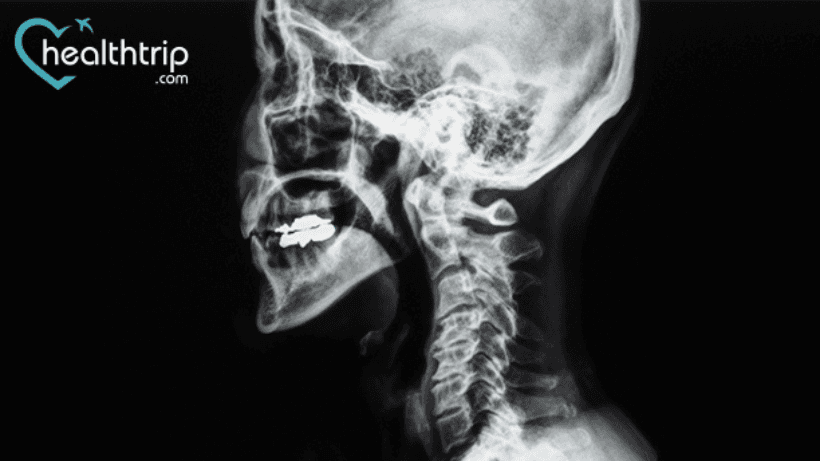

Anterior cervical diskectomy and fusion (ACDF) surgery is performed on your neck to remove damaged disks or bone spurs. And if you’re curious about how many years the outcome of such surgeries lasts, then you’re on the right page. Here we’ve discussed in brief its success rate and other facts that you need to know after undergoing such medical treatment.

ACDF improves outcomes for all primary diagnoses and has been shown to last for more than ten years. Secondary surgeries were performed to repair the pseudarthrosis and to treat symptomatic adjacent-level degeneration.